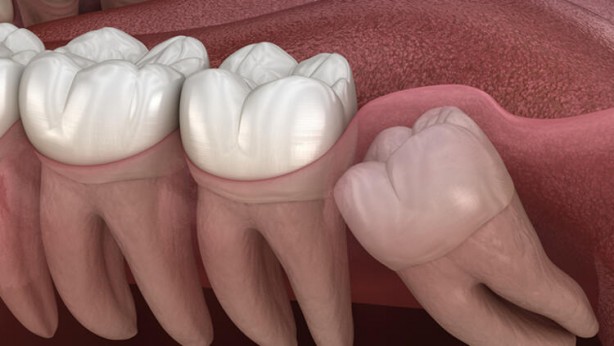

Diş çürüklerinin ortaya çıkış süreci yanlış fırçalamadır.

Unutulmamalıdır ki çürük erken aşamada tespit edilirse geri döndürülebilir.